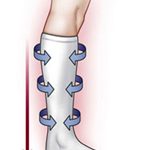

Varis Çorabı: İlaç tedavisi dışında DVT tedavisinin en önemli basamağı varis çorabıdır. Çorap 30-40

mmHg basınçta ve dizaltı düzeyine ulaşacak uzunlukta olmalıdır. İlk bir kaç gün sürekli, sonraları ise sadece gündüzleri varis çorabı giyilmelidir. Çorap yataktan kalmadan ayağa geçirilmelidir ve akşam yatıldığında çıkartılımalıdır. Çorap en az 2 yıl giyilmelidir. İlk günlerde bacakları kalp düzeyinin üzerine kaldırarak istirahat etmek bacaktaki şikayeti azaltır.